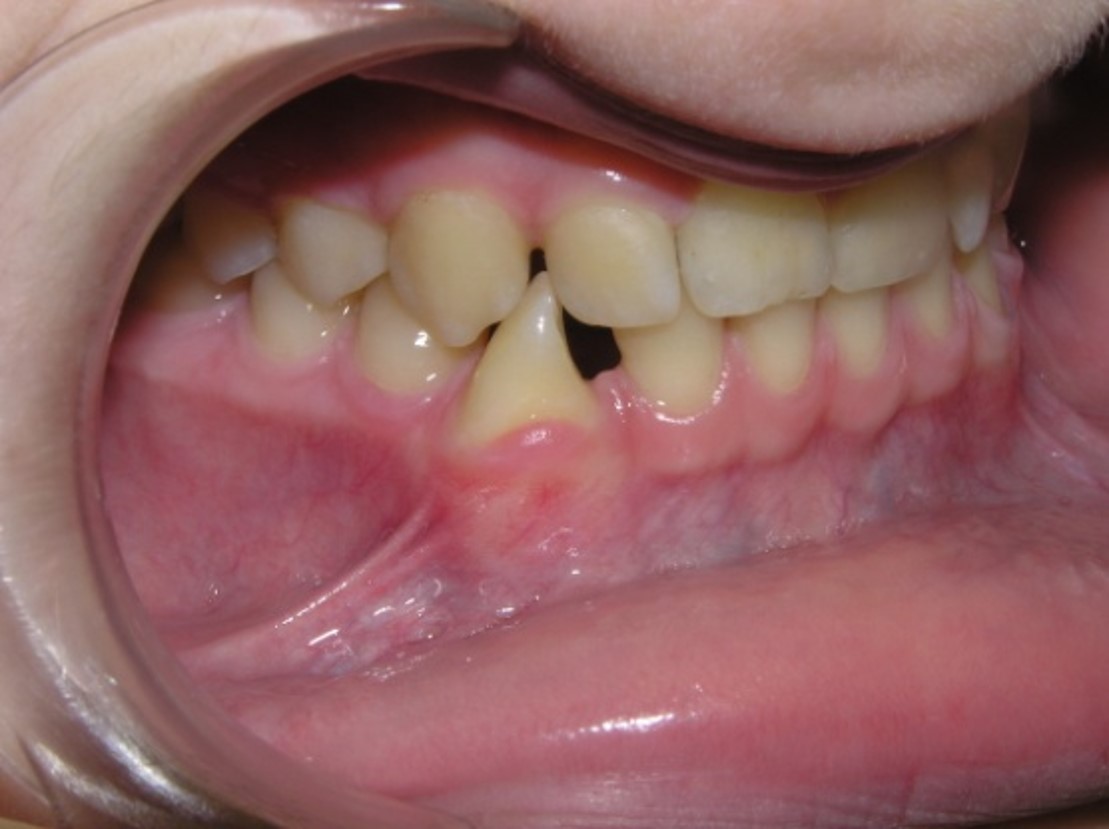

Tortoocclusion of teeth (rotation)

Pic.20. Tortoocclusion of teeth 11 and 21.